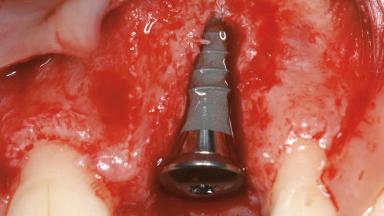

In September 2004, a 38-year-old female patient, a nonsmoker, was referred to our clinic for the replacement of the missing left central maxillary incisor (tooth 21),which had been removed two months before the initial appointment due to a vertical root fracture. The dental patient history revealed that the tooth in question had supported a ceramo-metal crown for more than ten years before the root fracture occurred. Implant therapy (single-tooth replacement) was considered the first therapeutic choice, as the neighboring teeth did not require significant restoration. The patient was in good general health, and her medical history revealed no significant findings.